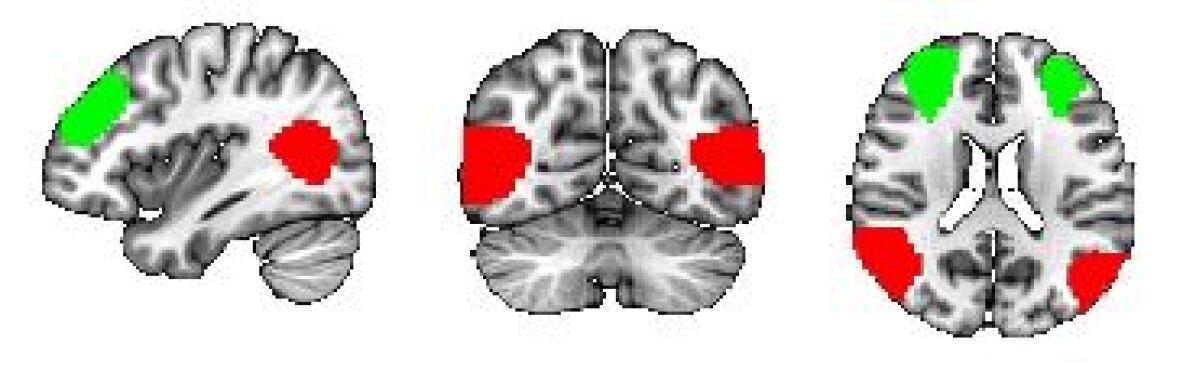

To identify the top ROIs for the intelligence prediction tasks, we first extracted the pooled ROIs after passing through the first layer of TopK Pool layer of a fully trained model using a holdout test set. We then selected the ROIs with highest frequency across each of the samples for all the intelligence scores. For fluid intelligence, we selected two ROIs (Middle Temporal Gyrus, and Middle Frontal Gyrus) (Fig 2(a)) with 90% frequency threshold. Similarly, for crystallized intelligence, middle frontal gyrus and caudate were selected with a frequency threshold of 90% (Fig 2(b)). For total composite scores, as the pooling ratio from hyper-parameter tuning was higher (0.78), we were able to extract 21 brain regions for 95% frequency. We categorized the selected regions into seven connectivity networks and plotted them independently in Fig. 3.

Refer to caption

(a) Cognitive Control Network

(b) Default Mode Network

(c) Sensorimotor Network

(d) Subcortical Network

(e) Visual Network

(f) Cerebellar Networks

Figure 3: Significant regions expressed as Connectivity Networks for Total Composite Scores

The diverse set of brain regions identified as relevant for total composite score reflects the intricate and distributed nature of cognitive processes, as well as the general and broad attribute of ’intelligence’. These regions cover six relatively separate brain networks. Sensorimotor network (postcentral gyrus) and visual network(middle/inferior occipital gyri, calcarine cortex, cuneus, fusiform) involve basic functions of various sensory inputs (J;Tadi ) and further integration of inputs (BrainMadeSimple (2022)). The cognitive control network covers particularly frontal-parietal regions (superior/middle frontal gyri, supplementary motor area, insula, hippocampal) and participates in various higher-order cognitive processes (Jacques et al. (2018)), such as executive function, attention, working memory, and planning (Tanji and Shima (1994)). The default network comprises the anterior cingulate cortex, posterior cingulate cortex, and precuneus and reflects the brain’s intrinsic activity in contrast to task-oriented controls (Zanto and Gazzaley (2013)). Their functions are linked to self-referential thinking (Raichle (2015)), introspection, and episodic memory retrieval (Gusnard et al. (2001)). Subcortical network, precisely caudate as discussed before has a role in learning and memory and has been shown to be able to predict IQ (Vincent et al. (2006)). Last but not the least is the cerebellum. Its function is well recognized to be beyond motor function, but subserving cognition (Koziol et al. (2011)), and recently cerebellum has been partitioned to echo the 7 cortical networks (King et al. (2019)). In summary, the interplay of these diverse brain regions likely contributes to the complexity of cognitive processes that manifest as Total Composite Scores. The extensive network of regions suggests that intelligence is not confined to a single brain area but rather emerges from the collaboration of numerous interconnected regions, each contributing its unique specialization to overall cognitive performance.